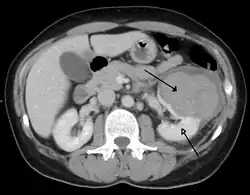

| Trauma abdominal resultando em uma contusão no rim direito (seta aberta) e sangue ao redor do rim (seta fechada), conforme visto em tomografia computadorizada. | |